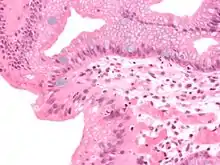

Both macroscopic (from endoscopy) and microscopic positive findings are required to make a diagnosis. Barrett's esophagus is marked by the presence of columnar epithelia in the lower esophagus, replacing the normal squamous cell epithelium—an example of metaplasia. The secretory columnar epithelium may be more able to withstand the erosive action of the gastric secretions; however, this metaplasia confers an increased risk of adenocarcinoma.[15]

Intestinal metaplasia

The presence of goblet cells, called intestinal metaplasia, is necessary to make a diagnosis of Barrett's esophagus. This frequently occurs in the presence of other metaplastic columnar cells, but only the presence of goblet cells is diagnostic. The metaplasia is grossly visible through a gastroscope, but biopsy specimens must be examined under a microscope to determine whether cells are gastric or colonic in nature. Colonic metaplasia is usually identified by finding goblet cells in the epithelium and is necessary for the true diagnosis.